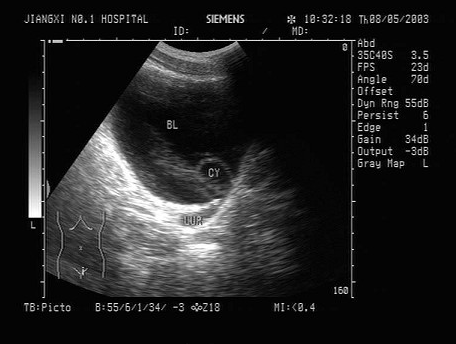

女性,5岁,超声检查如图所示,最可能的诊断是()。

A . 输尿管脱垂

B . 输尿管憩室

C . 输尿管囊肿

D . 输尿管肿瘤

E . 巨输尿管症